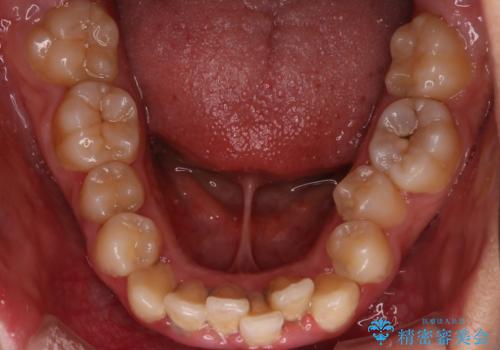

- 「前歯が出ていて並びも悪いのが気になる」との主訴で来院されました。診察の結果、上顎前歯の前突と中等度の叢生(ガタつき)が認められ、歯がきれいに並ぶスペースが不足していました。横顔のバランスと歯並びの両方を整えるため、上顎の左右の第一小臼歯2本を抜歯し、前歯を内側に下げながら歯列全体を整える治療計画を立てました。

患者さんのご希望もあり、取り外しが可能で目立ちにくいインビザライン(マウスピース矯正)を選択。抜歯スペースを活用しながら、叢生と前突感の改善を同時に目指しました。

治療はインビザラインによって進め、抜歯スペースを使って前歯を内側に引き込みながら、歯のガタつきも順に整えていきました。初期の段階で前歯の見た目が大きく変わり、患者さんにも「印象が柔らかくなった」と非常に喜んでいただけました。

しかし、途中で来院が途絶えてしまい、インビザラインのアカウント(治療管理期間)が終了。再発注やリカバリーが難しくなったため、治療再開のためにワイヤー矯正の提案を行いましたが、患者さんのご希望により再治療は見送られることとなりました。

インビザラインは高い効果が期待できる一方、継続的な来院と装着が不可欠な治療法です。継続していればさらに良い結果が得られたと考えられるケースでした。